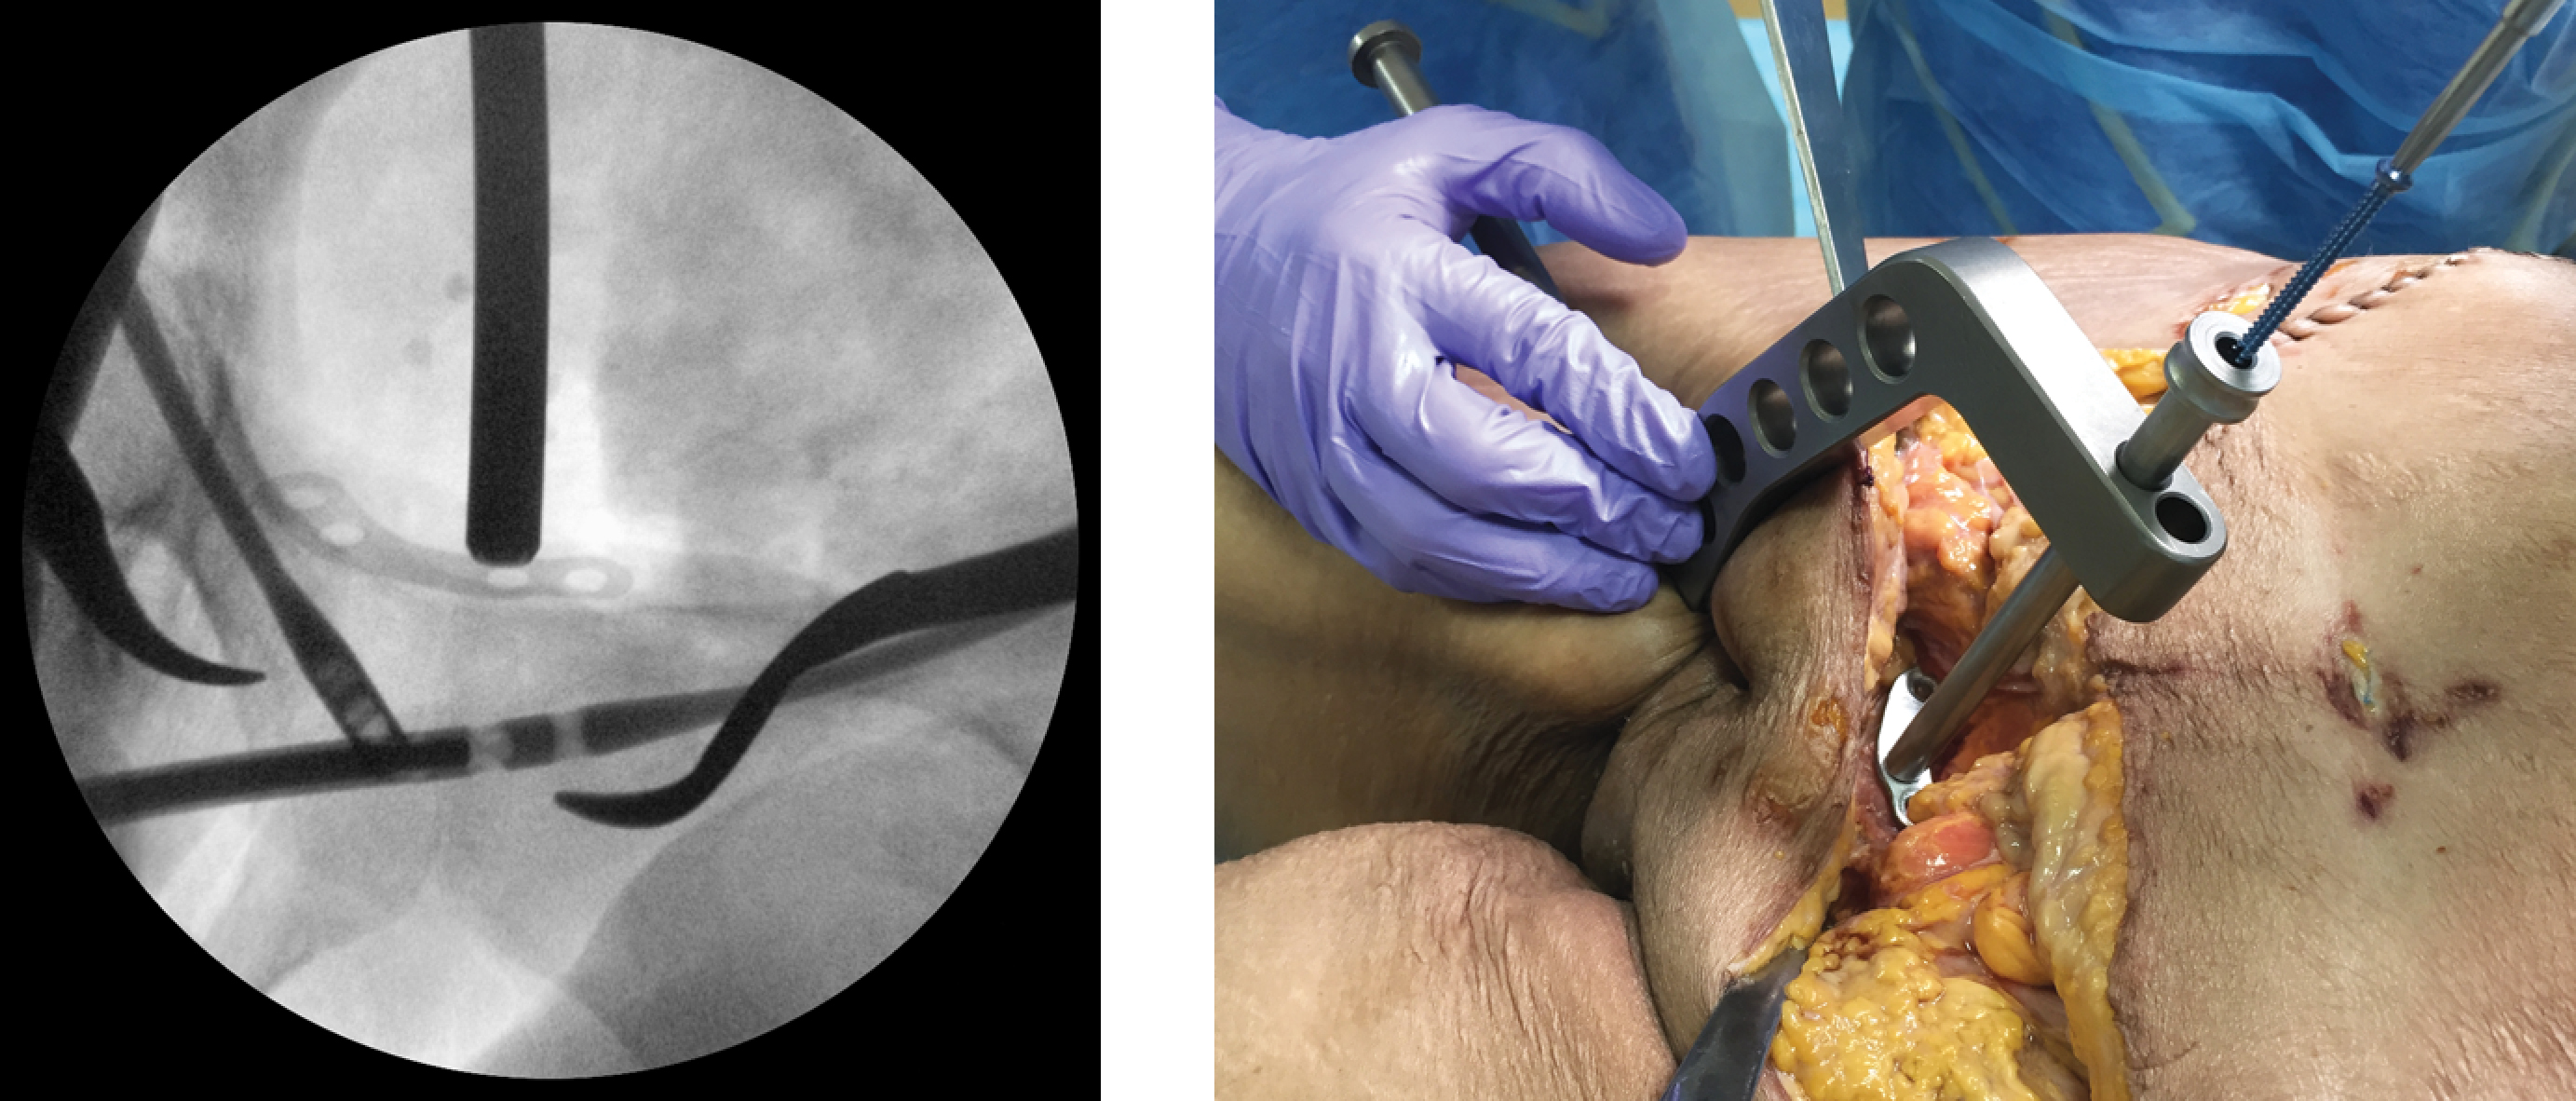

Sequential fixation of the pubic rami fractures was then performed using locking nails on both sides through a 1-cm contralateral skin puncture located below the Pfannenstiel incision, but without inserting the locking screws. Without removing the guide from the last inserted nail, the plate was positioned so that the midpoint of the implant lay exactly over the reduced pubic symphysis (Figure 3).

Figure 3. Intraoperative inlet view of the pelvic with nails inserted into both pubic bones (a); the plate is positioned at the midpoint of the superior symphyseal border via the surgical approach (b)